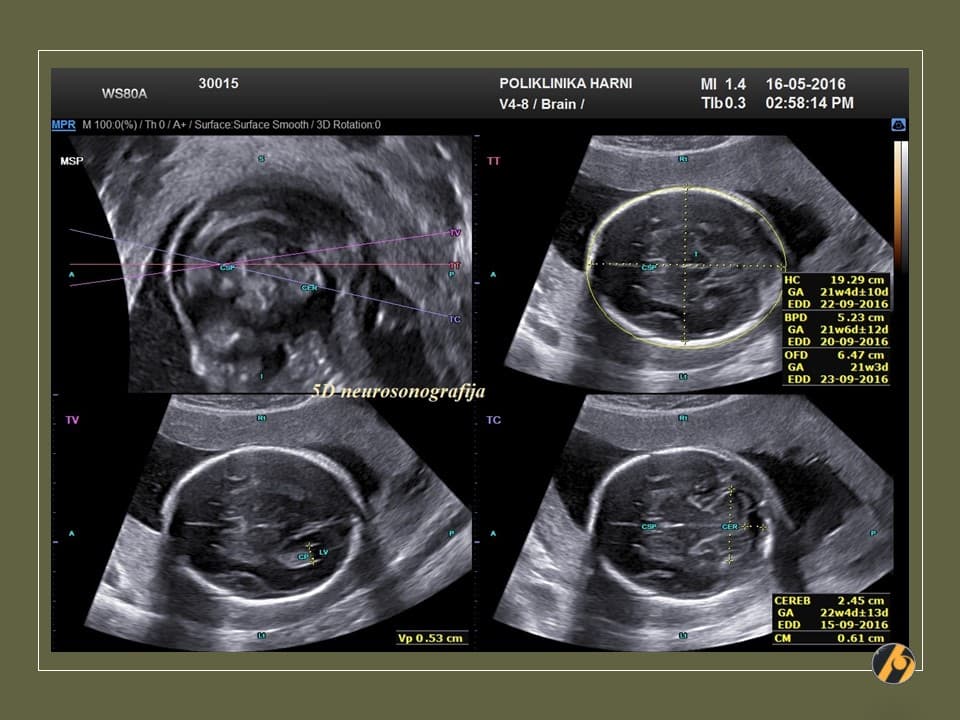

Ovaj pregled omogućuje liječniku da procijeni razvija li se beba uredno te pruža važan uvid u tijek trudnoće, kao i da preporuči dodatne pretrage kao što su fetalna neurosonografija ili fetalna ehokardiografija.